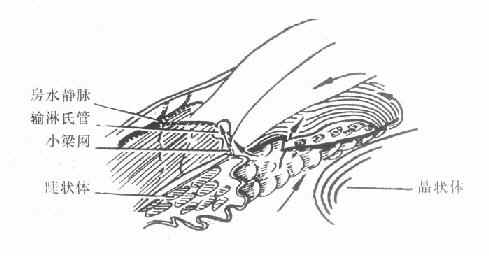

急性闭角型青光眼虽可用药物治疗使急性发作缓解,达到短期降压的目的,但不能防止再发。因此眼压下降后应根据病情,特别是前房角情况,尽快选择周边虹膜切除术或滤过性手术(图10-4)。

图10-3 闭角青光眼虹膜切除术后

(前房加深,房水经周边虹膜切除口进入前房)